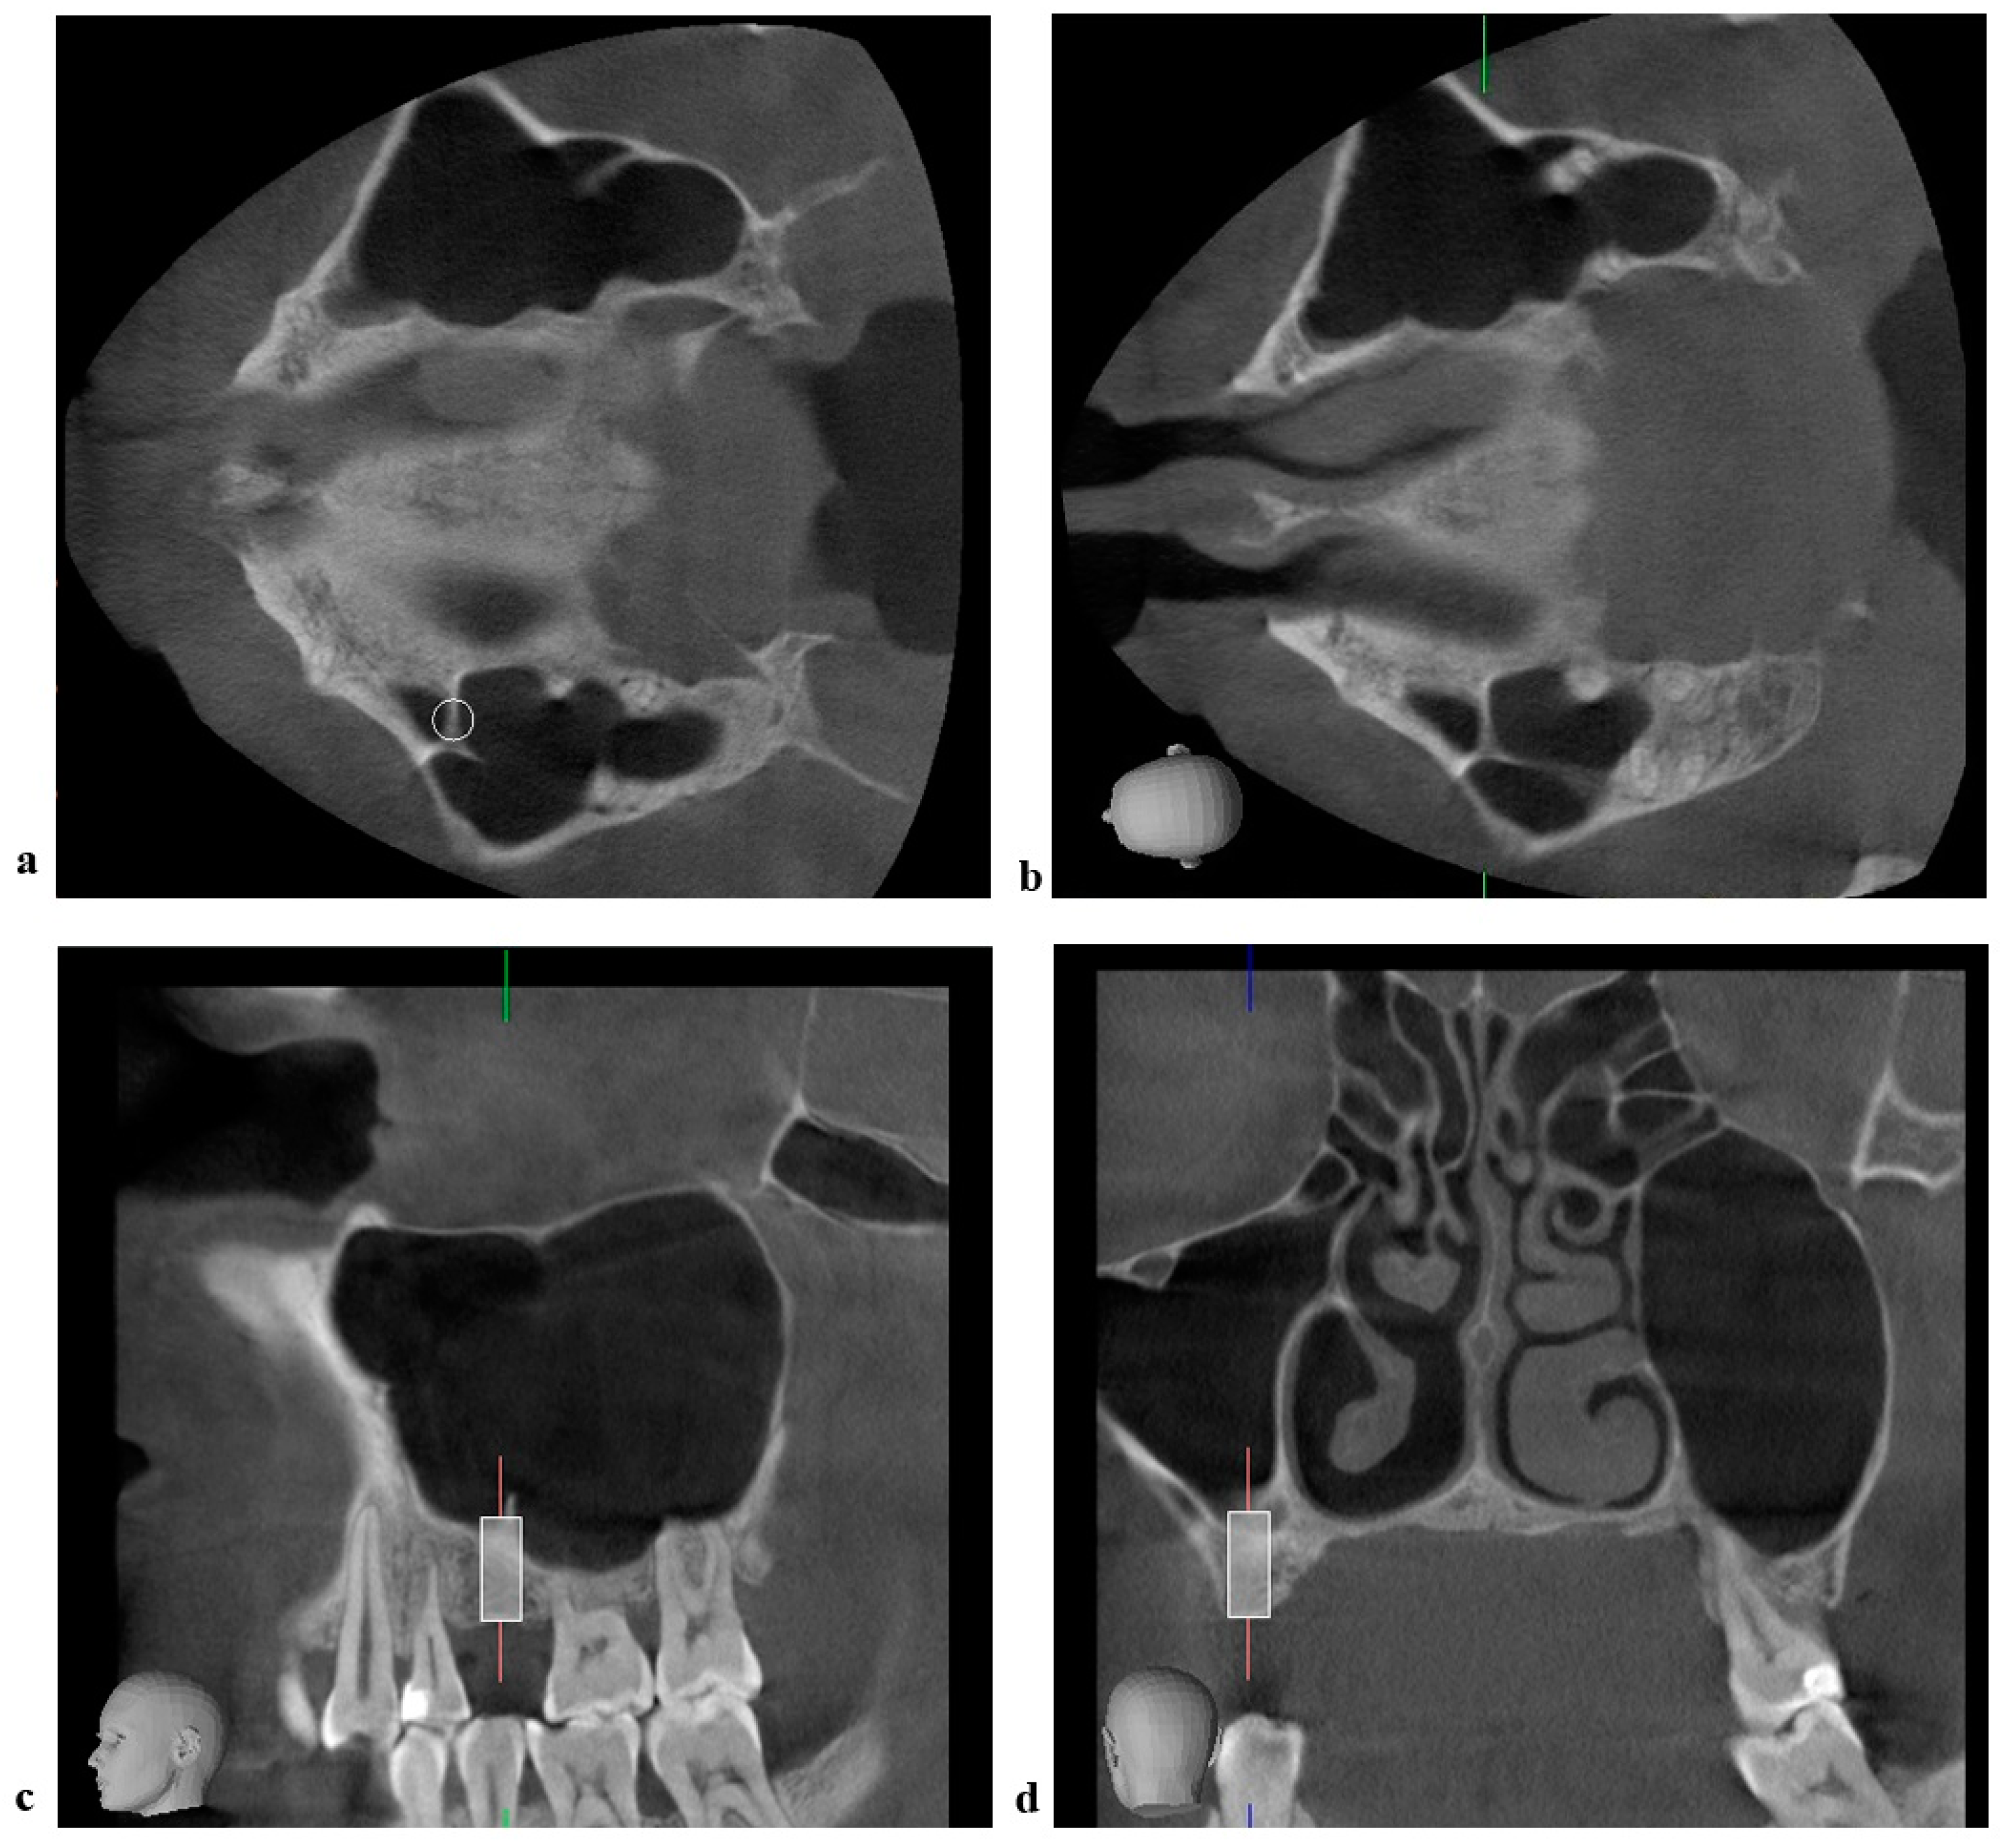

2.3. Radiographic Measurements